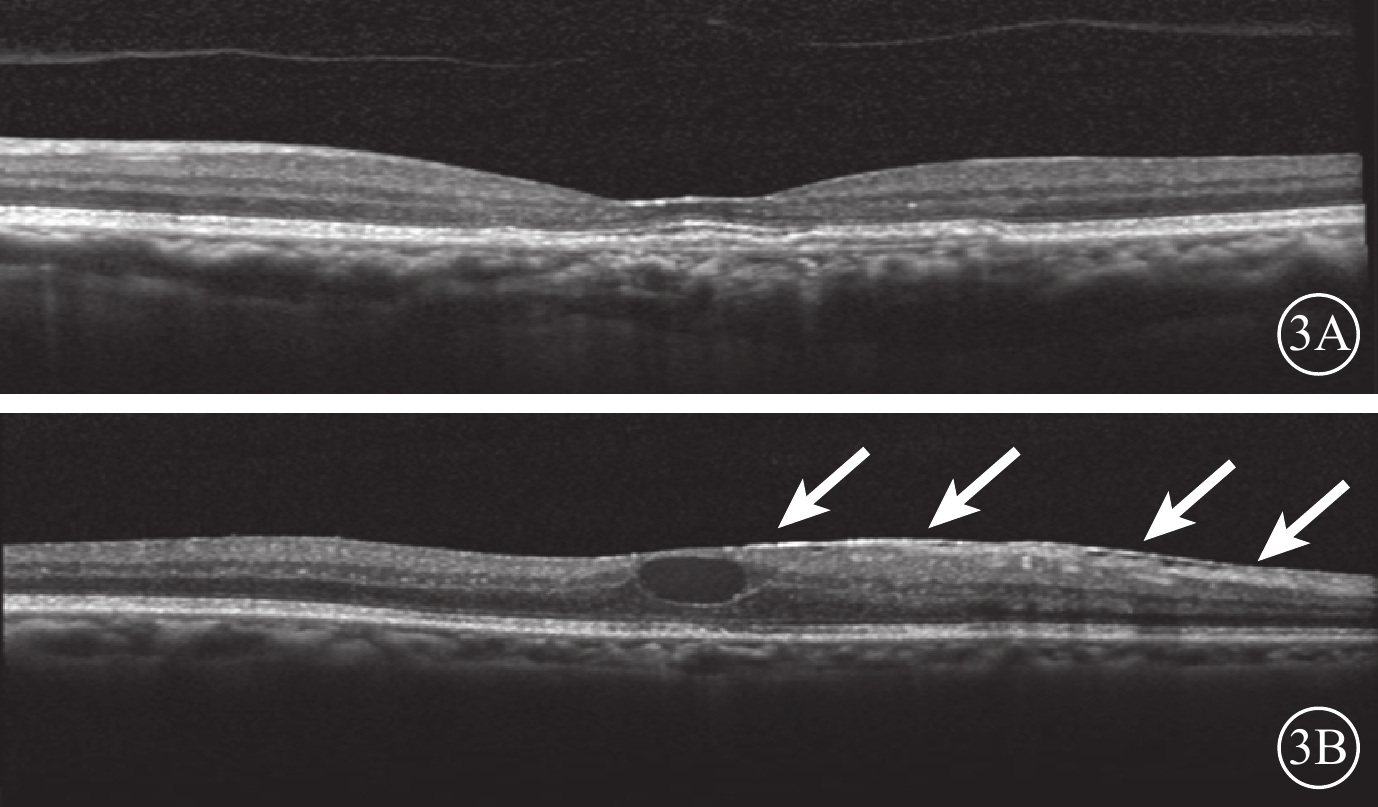

所有患者均采用3+PRN的方式接受玻璃體腔注射抗VEGF藥物治療。治療前采用OCT觀察患者雙眼的VMI情況。以中心凹為中心,掃描黃斑區,使用高速模式。(1)體積掃描:ART疊加次數9次,97線掃描線,20°×20°;(2)十字掃描:ART疊加次數36次,2線掃描線,20°×20°。將存在玻璃體黃斑粘連(VMA)、黃斑前膜(MEM)、完全性玻璃體后脫離(C-PVD)定義為VMI異常。以玻璃體粘附在中心凹中心3 mm直徑內,但部分玻璃體視網膜分離為VMA;并根據OCT圖像上玻璃體與黃斑部粘附的直徑大小將VMA分為局灶型(≤1500 μm)和廣泛型(>1500 μm)[17]。以鄰近或貼覆在黃斑前、較玻璃體后界膜厚且反射性強的組織為MEM[18]。以玻璃體后界膜高起,與視網膜黃斑無粘附為C-PVD[19-21]。34只研究眼中,存在VMI異常(圖1)12只眼。其中,廣泛型VMA 8只眼,局灶型VMA 3只眼,MEM 1只眼;合并存在局灶型VMA、MEM 1只眼。34只對照眼中,存在VMI異常(圖2)12只眼。其中,廣泛型VMA 7只眼,局灶型VMA 2只眼,C-PVD 2只眼,MEM 1只眼。治療后隨訪觀察12~26個月,平均隨訪時間16.4個月。隨訪期間每月用隨訪模式進行雙眼OCT檢查。對比分析患者雙眼治療前后VMI的變化情況。

VMI異常的研究眼OCT像。1A. 黃斑中心凹區域局灶型VMA(白箭);1B. MEM(白箭)

VMI異常的研究眼OCT像。1A. 黃斑中心凹區域局灶型VMA(白箭);1B. MEM(白箭)

所有患者均采用3+PRN的方式接受玻璃體腔注射抗VEGF藥物治療。治療前采用OCT觀察患者雙眼的VMI情況。以中心凹為中心,掃描黃斑區,使用高速模式。(1)體積掃描:ART疊加次數9次,97線掃描線,20°×20°;(2)十字掃描:ART疊加次數36次,2線掃描線,20°×20°。將存在玻璃體黃斑粘連(VMA)、黃斑前膜(MEM)、完全性玻璃體后脫離(C-PVD)定義為VMI異常。以玻璃體粘附在中心凹中心3 mm直徑內,但部分玻璃體視網膜分離為VMA;并根據OCT圖像上玻璃體與黃斑部粘附的直徑大小將VMA分為局灶型(≤1500 μm)和廣泛型(>1500 μm)[17]。以鄰近或貼覆在黃斑前、較玻璃體后界膜厚且反射性強的組織為MEM[18]。以玻璃體后界膜高起,與視網膜黃斑無粘附為C-PVD[19-21]。34只研究眼中,存在VMI異常(圖1)12只眼。其中,廣泛型VMA 8只眼,局灶型VMA 3只眼,MEM 1只眼;合并存在局灶型VMA、MEM 1只眼。34只對照眼中,存在VMI異常(圖2)12只眼。其中,廣泛型VMA 7只眼,局灶型VMA 2只眼,C-PVD 2只眼,MEM 1只眼。治療后隨訪觀察12~26個月,平均隨訪時間16.4個月。隨訪期間每月用隨訪模式進行雙眼OCT檢查。對比分析患者雙眼治療前后VMI的變化情況。

VMI異常的研究眼OCT像。1A. 黃斑中心凹區域局灶型VMA(白箭);1B. MEM(白箭)

VMI異常的研究眼OCT像。1A. 黃斑中心凹區域局灶型VMA(白箭);1B. MEM(白箭)